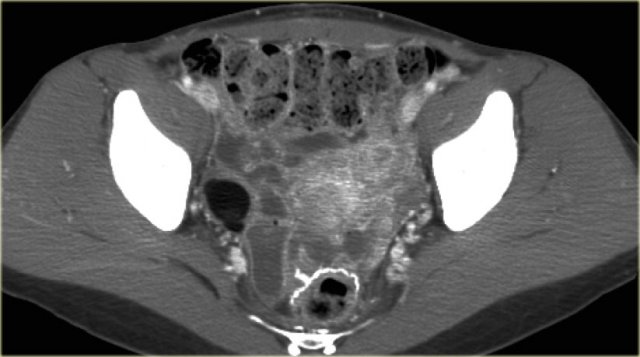

On ultrasound both ovaries are markedly enlarged and contain cystic components with intracystic solid components (arrows).

The complex solid-cystic lesions, in addition to being bilateral, are suspicious for a cystic ovarian neoplasm and warrant further evaluation.

Again, the role of imaging is to confirm a lesion is present and to decide that this is not a lesion that can be classified as definitely benign nor a lesion that can be safely followed-up: action is required.

CT of the same patient confirms large bilateral complex solid-cystic lesions, bulging into the abdomen.

The purpose of the CT is not to confirm what was already known from the ultrasound, but to stage disease.

On the basis of CT (or of MRI) it is not possible to determine the histologic type of the tumor.

This is not relevant. This patient will undergo surgery.

For epithelial tumors - by far the most common group of malignant ovarian tumors - even after surgery, the exact tumor subtype is much less important for the prognosis than factors such as FIGO-stage, tumor differentation grade, and how succesful surgery was in removing all of the disease.

For this patient the relevant findings are on the image on the left.

There is a peritoneal implant.

The tumor was resected and pathology showed this was an endometrioid ovarian carcinoma.